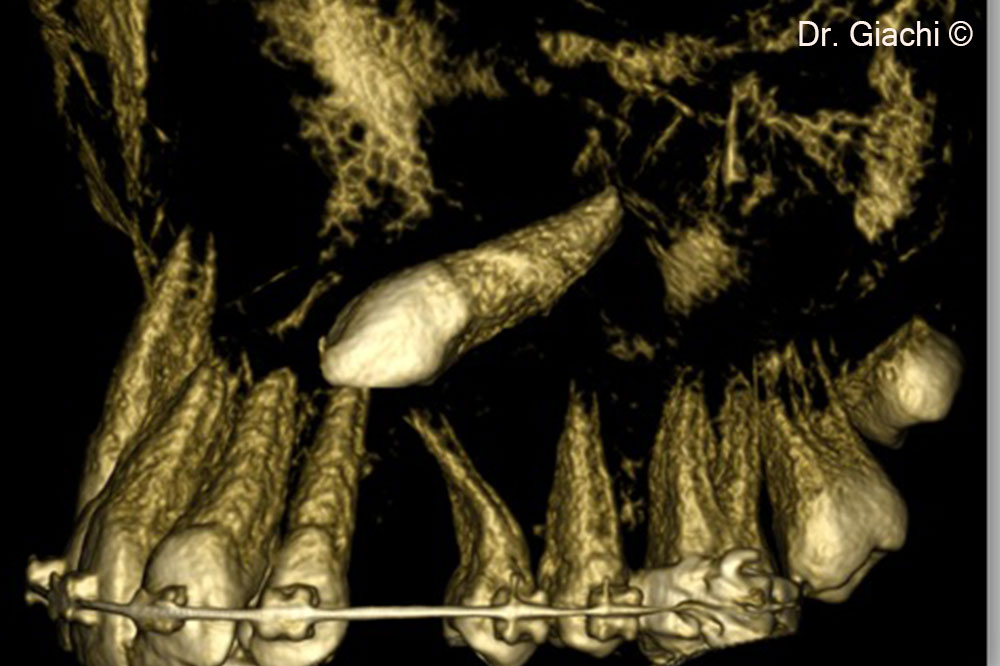

Một bệnh nhân nam (16 tuổi) có răng nanh trên không thể phục hồi bằng phương pháp chỉnh nha truyền thống.